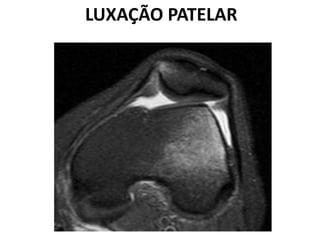

LUXAÇÃO PATELAR